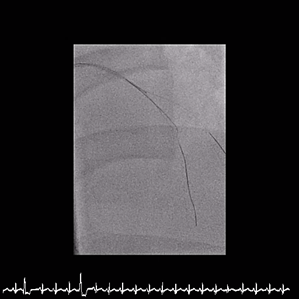

Inrefractory VT/VF arrest and cardiogenic shock, emergent culprit RCA PCI wasperformed under VA-ECMO and IABP. A Conquest Pro 12 GW crossed the distal RCACTO after failed attempts with Fielder FC and Gaia 2nd. Sequential POBA wasdone, followed by three BMS from RCA-M to RCA-PL, achieving TIMI 3 flow. Abrief attempt to wire LAD-P CTO with a Fielder XT-R failed, suggesting achronic occlusion, and the procedure was stopped due to instability. Afterneurological recovery, staged LAD CTO PCI was performed. Angiography confirmedLAD-P CTO with a blunt stump, severe LCX disease, and patent RCA stents.Antegrade wiring was initiated with an XB 3.5/7Fr GC. A Gaia 2nd entered aseptal branch using a Trek 1.2¡¿6 mm OTW BC. With APT 1.9Fr and Sasuke MCs,multiple GWs (XT-A, UB3, Conquest Pro 12) attempted proximal cap penetrationbut tracked into false lumens. IVUS from septal and D1 branches was used forcap clarification but remained inconclusive. Usingan IVUS-guided parallel-wire approach, a Progress 200T achieved true–false–truecrossing into distal LAD. Sequential 1.0–2.5 mm BC dilatation prepared thevessel. Given a Medina 1,1,1 LAD–D1 bifurcation, a DK-Crush technique waschosen. A Synergy 2.5¡¿48 mm DES was deployed from LAD-M to LAD-D, crushed,rewired, and optimized. A second 2.5¡¿48 mm DES was placed from LAD-P to D1,followed by kissing balloons and final POT. Final angiography showed TIMI 3flow with good expansion.